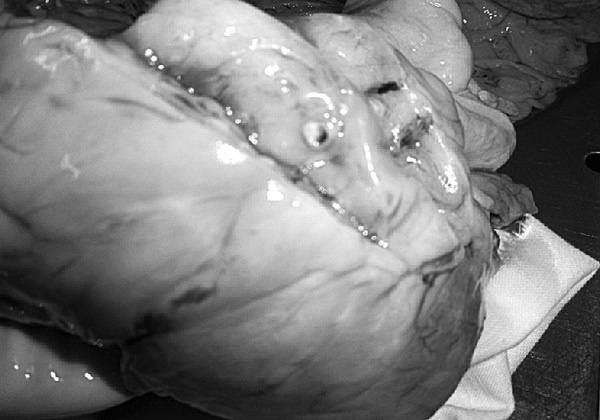

Постинфарктный кардиосклероз